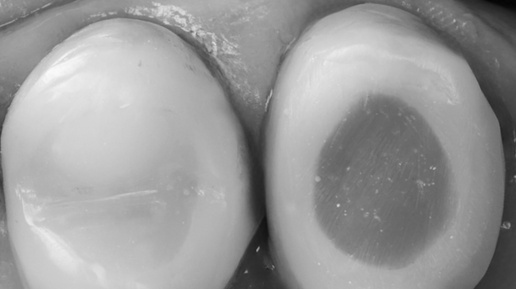

Микроскоп - остатки прошлого материала в каналах при повторном эндо